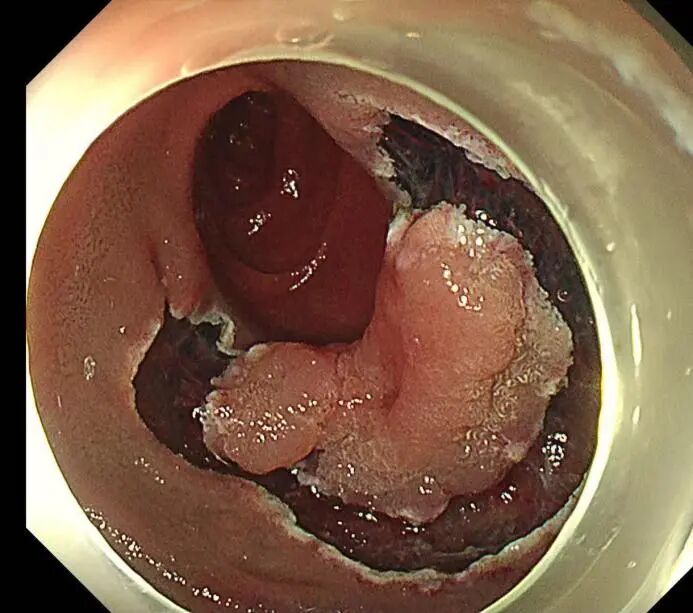

近日,上海市东方医院徐美东教授团队成功为一例73岁患者实施内镜下手术,切除了位于十二指肠降部、约3.5×2.5cm的侧向发育型肿瘤(LST),这一病变犹如一片去壳的完整牡蛎,以其扁平却颇具厚度的形态在被称为“手术禁区”的十二指肠降部的狭小肠腔内形成了巨大挑战。如今,在创新技术的助力下,这一难题被轻松攻克。

手术开始,尽管十二指肠降部空间有限,病变较大,且十二指肠部位血供丰富,但在SPEED技术的辅助下,徐美东教授用稳定的控镜和精妙的微操,如“庖丁解牛”般逐步推进,边注射边剥离,全程视野清晰可见,最终仅耗时半小时将该病变整体剥离并完整取出,完成这场“刀尖上的舞蹈”。创面干净、几乎无出血,没有丝毫肌层损伤,堪称内镜手术的“完美范本”。

1-位于十二指肠降部占管腔1/2圈的病变

2-SPEED技术边注射边剥离